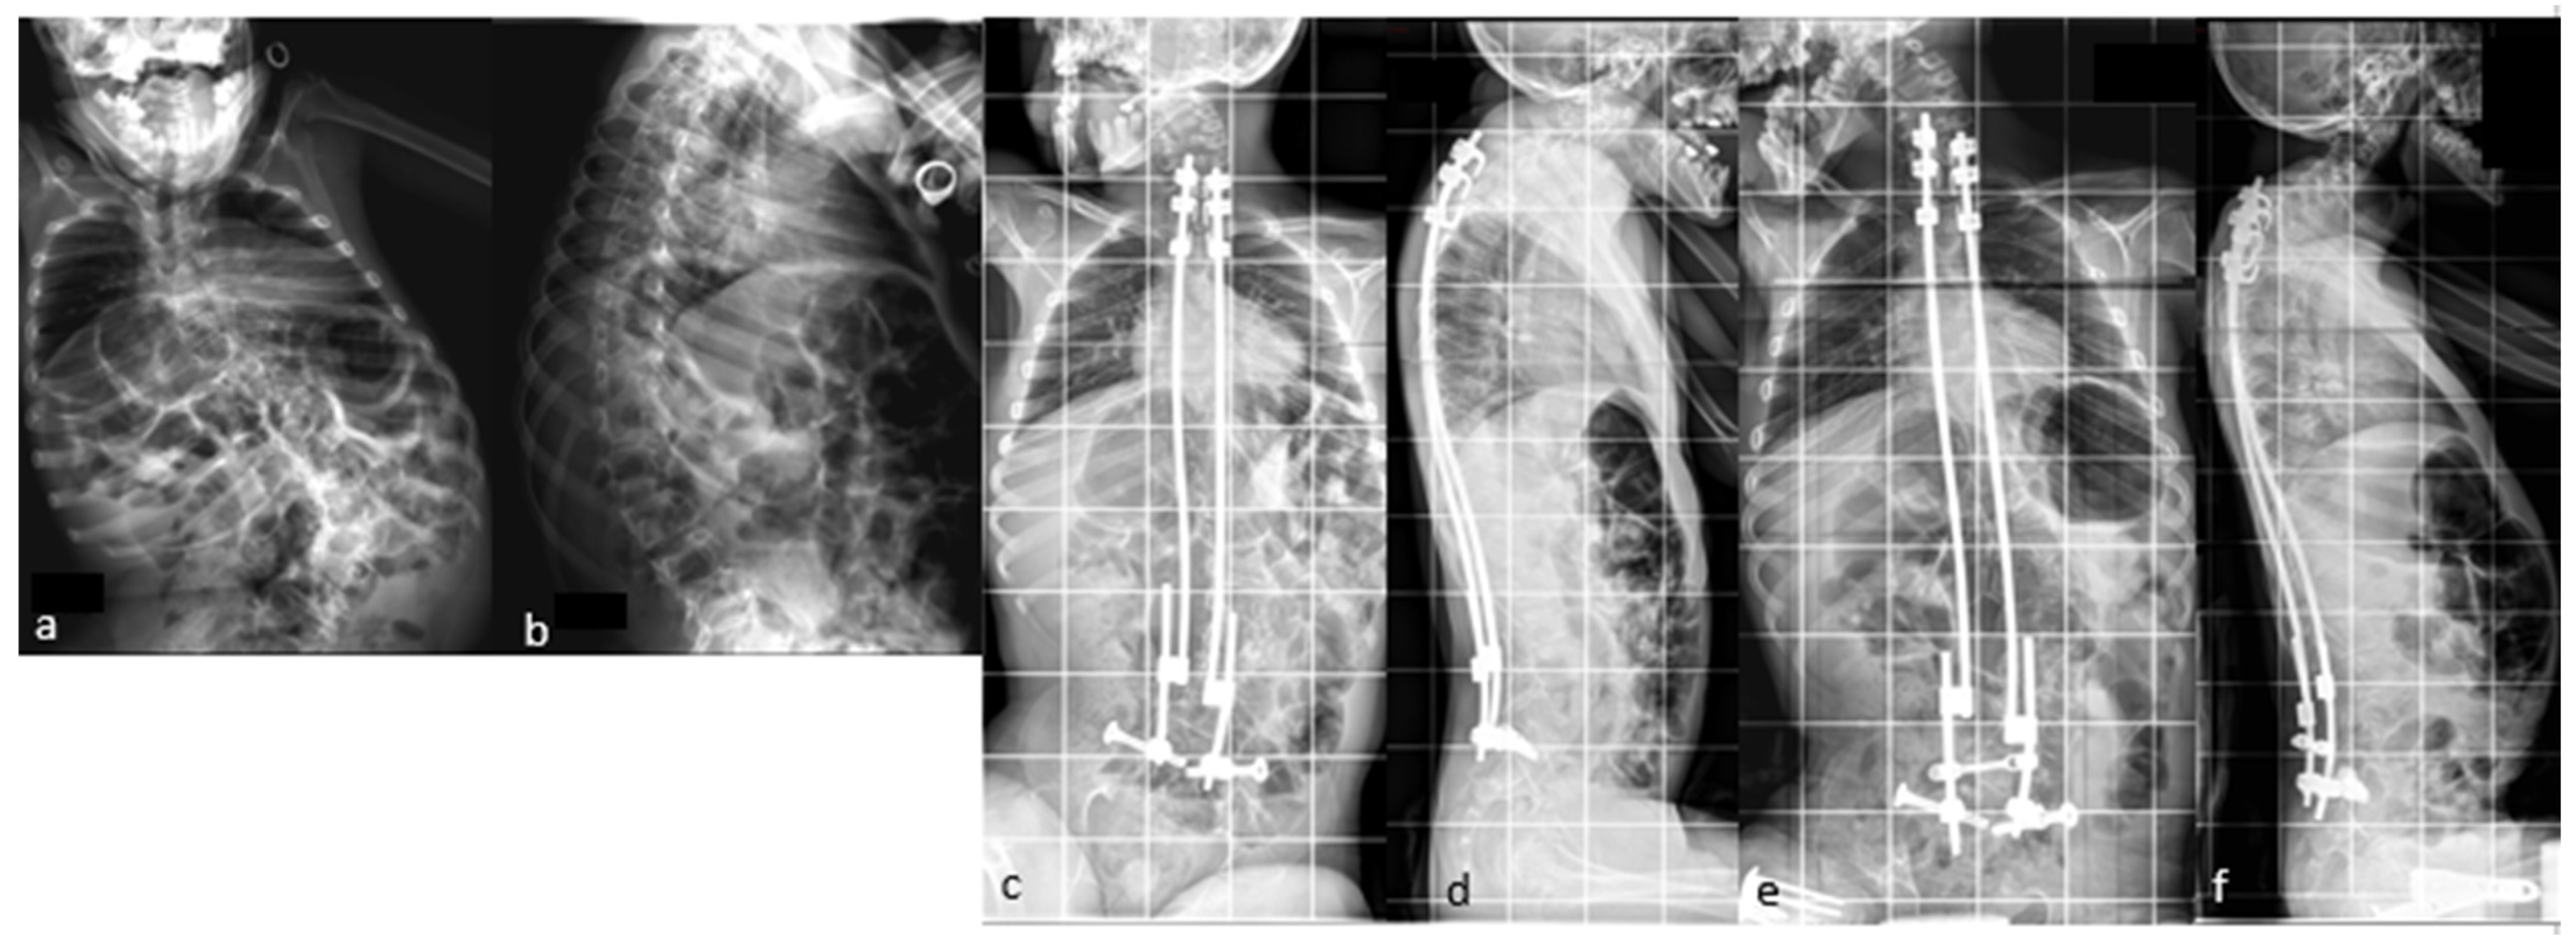

The case shown in the first figure is a boy with Morquio syndrome with severe kyphosis who underwent MIBF extended to the pelvis after 4 weeks of preoperative halo-gravity traction (Figure 1).

Figure 1. (ad) Preoperative radiographs and pictures of a 10-year-old boy with kyphosis due to Morquio syndrome; (eh) 2 year postoperative radiographs and pictures.